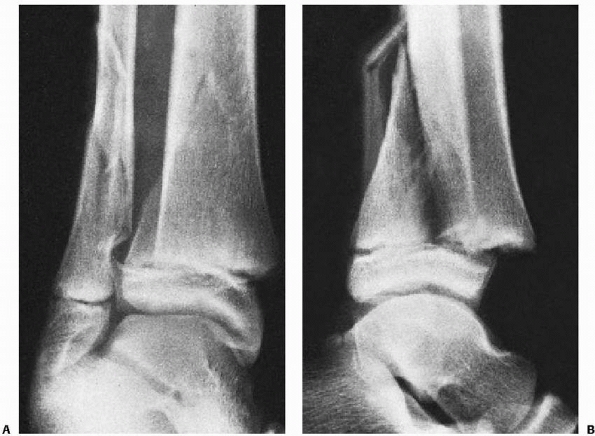

![]() |

FIGURE 26-11 A. Anteroposterior view of triplane fracture. On this view, the fracture appears to be a Salter-Harris type III configuration. B. Lateral view of triplane fracture. On this view, the fracture appears to be a Salter-Harris type II configuration. C. Three-dimensional CT reconstruction can demonstrate significant metaphyseal displacement. D. Three-dimensional CT reconstruction can demonstrate intra-articular displacement.

|

common the appearance of a Salter-Harris type III fracture on the

anteroposterior radiographs and of a Salter-Harris type II fracture on

the lateral radiographs (Fig. 26-11). CT scans can be very helpful to understand the complex anatomy of these fractures (see Fig. 26-11). It has been proposed that the mechanism of injury for Tillaux and triplane fractures is external rotation.47,148